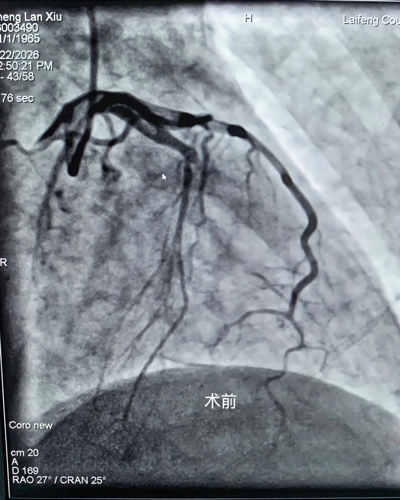

2026年2月22日,龙山县人民医院心内科接诊一名急性胸痛发病12小时患者,心电图诊断为急性广泛前壁心肌梗死,病情十分危重,需要紧急进行冠脉介入手术(PCI)开通血管抢救生命,恰巧导管室占台,龙山县人民医院心内科刘主任果断处理,紧急联系来凤县人民医院心内科朱兴彪主任,接到相关信息后,来凤县人民医院心内科团队立即启动“急性心肌梗死”救治流程及快速激活导管室,实行先诊疗后付费,绕行急诊科和CCU,全程绿色通道直达导管室进行急诊PCI术,手术D2B仅为26分钟,极大程度缩短抢救时间,挽救患者心肌。该患者于3月2日顺利康复出院,后期可在龙山县或来凤县进行门诊随访及治疗。